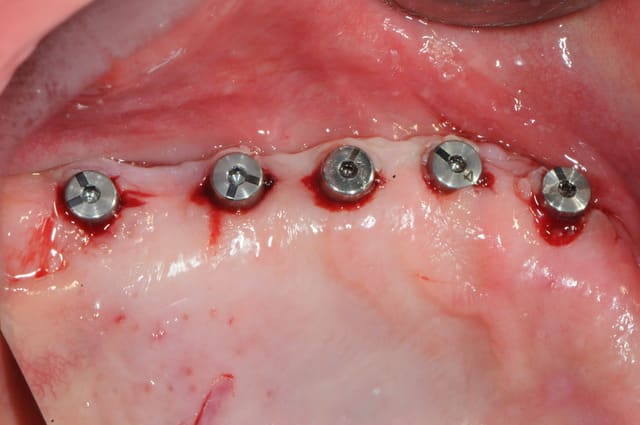

la pose des implants s'est faite dans de bonnes conditions; -j'ai pris une douche le matin, je me suis lavé les mains (tree time !), tout était stérile, ...

-pose des implants sans souci (à peine un petit Summers).

-pose d'une membrane de Collagène AT par dessus pour les quelques spires d'implants légèrement exposés.

prothèse complète mise en place puis 4 mois plus tard, mise en place des piliers coniques (genre multi-unit) pour faire une barre transvissée.